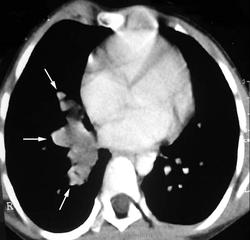

Бронхолегочные секвестрации

- участки нефункционирующей легочной ткани, не связаны с ТБД, снабжаются артериальной кровью из большого круга кровообращения

• Экстралобарная секвестрация

- кисты должны происходить из бронхов

- аберрантный сосуд отходит от аорты или ее ветвей

- патологический участок окружен собственным плевральным покровом

• Интралобарная секвестрация

- аберрантный сосуд отходит от аорты или ее ветвей

- секвестр. участок не имеет своего плеврального листка

- связи с окружающей легочной тканью через нормальные бронхи, артерии и вены нет

Необходимо выполнение КТ-ангиографии или МРА